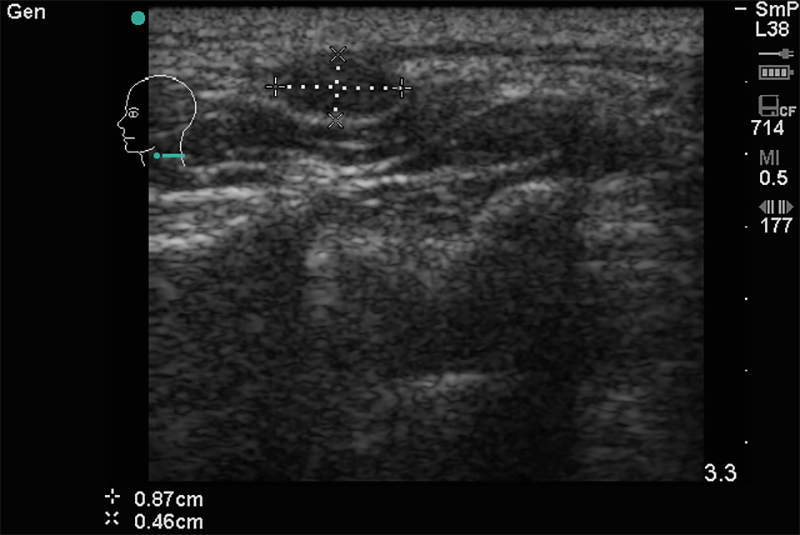

A nyaki, hónalji és ágyéki tájék nyirokcsomóinak gyulladásos vagy daganatos eredetû megnagyobbodásának kimutatására. Ha bármely testtájékon, vagy a felsorolt régiókban fájdalmas vagy fájdalommentes csomó ill. duzzanat jelenik meg, tisztázható, hogy az elváltozás nyirokcsomó vagy egyéb eltérés. Fontos tudni, hogy sok daganat első észlelhető tünete kóros nyirokcsomó megjelenése.